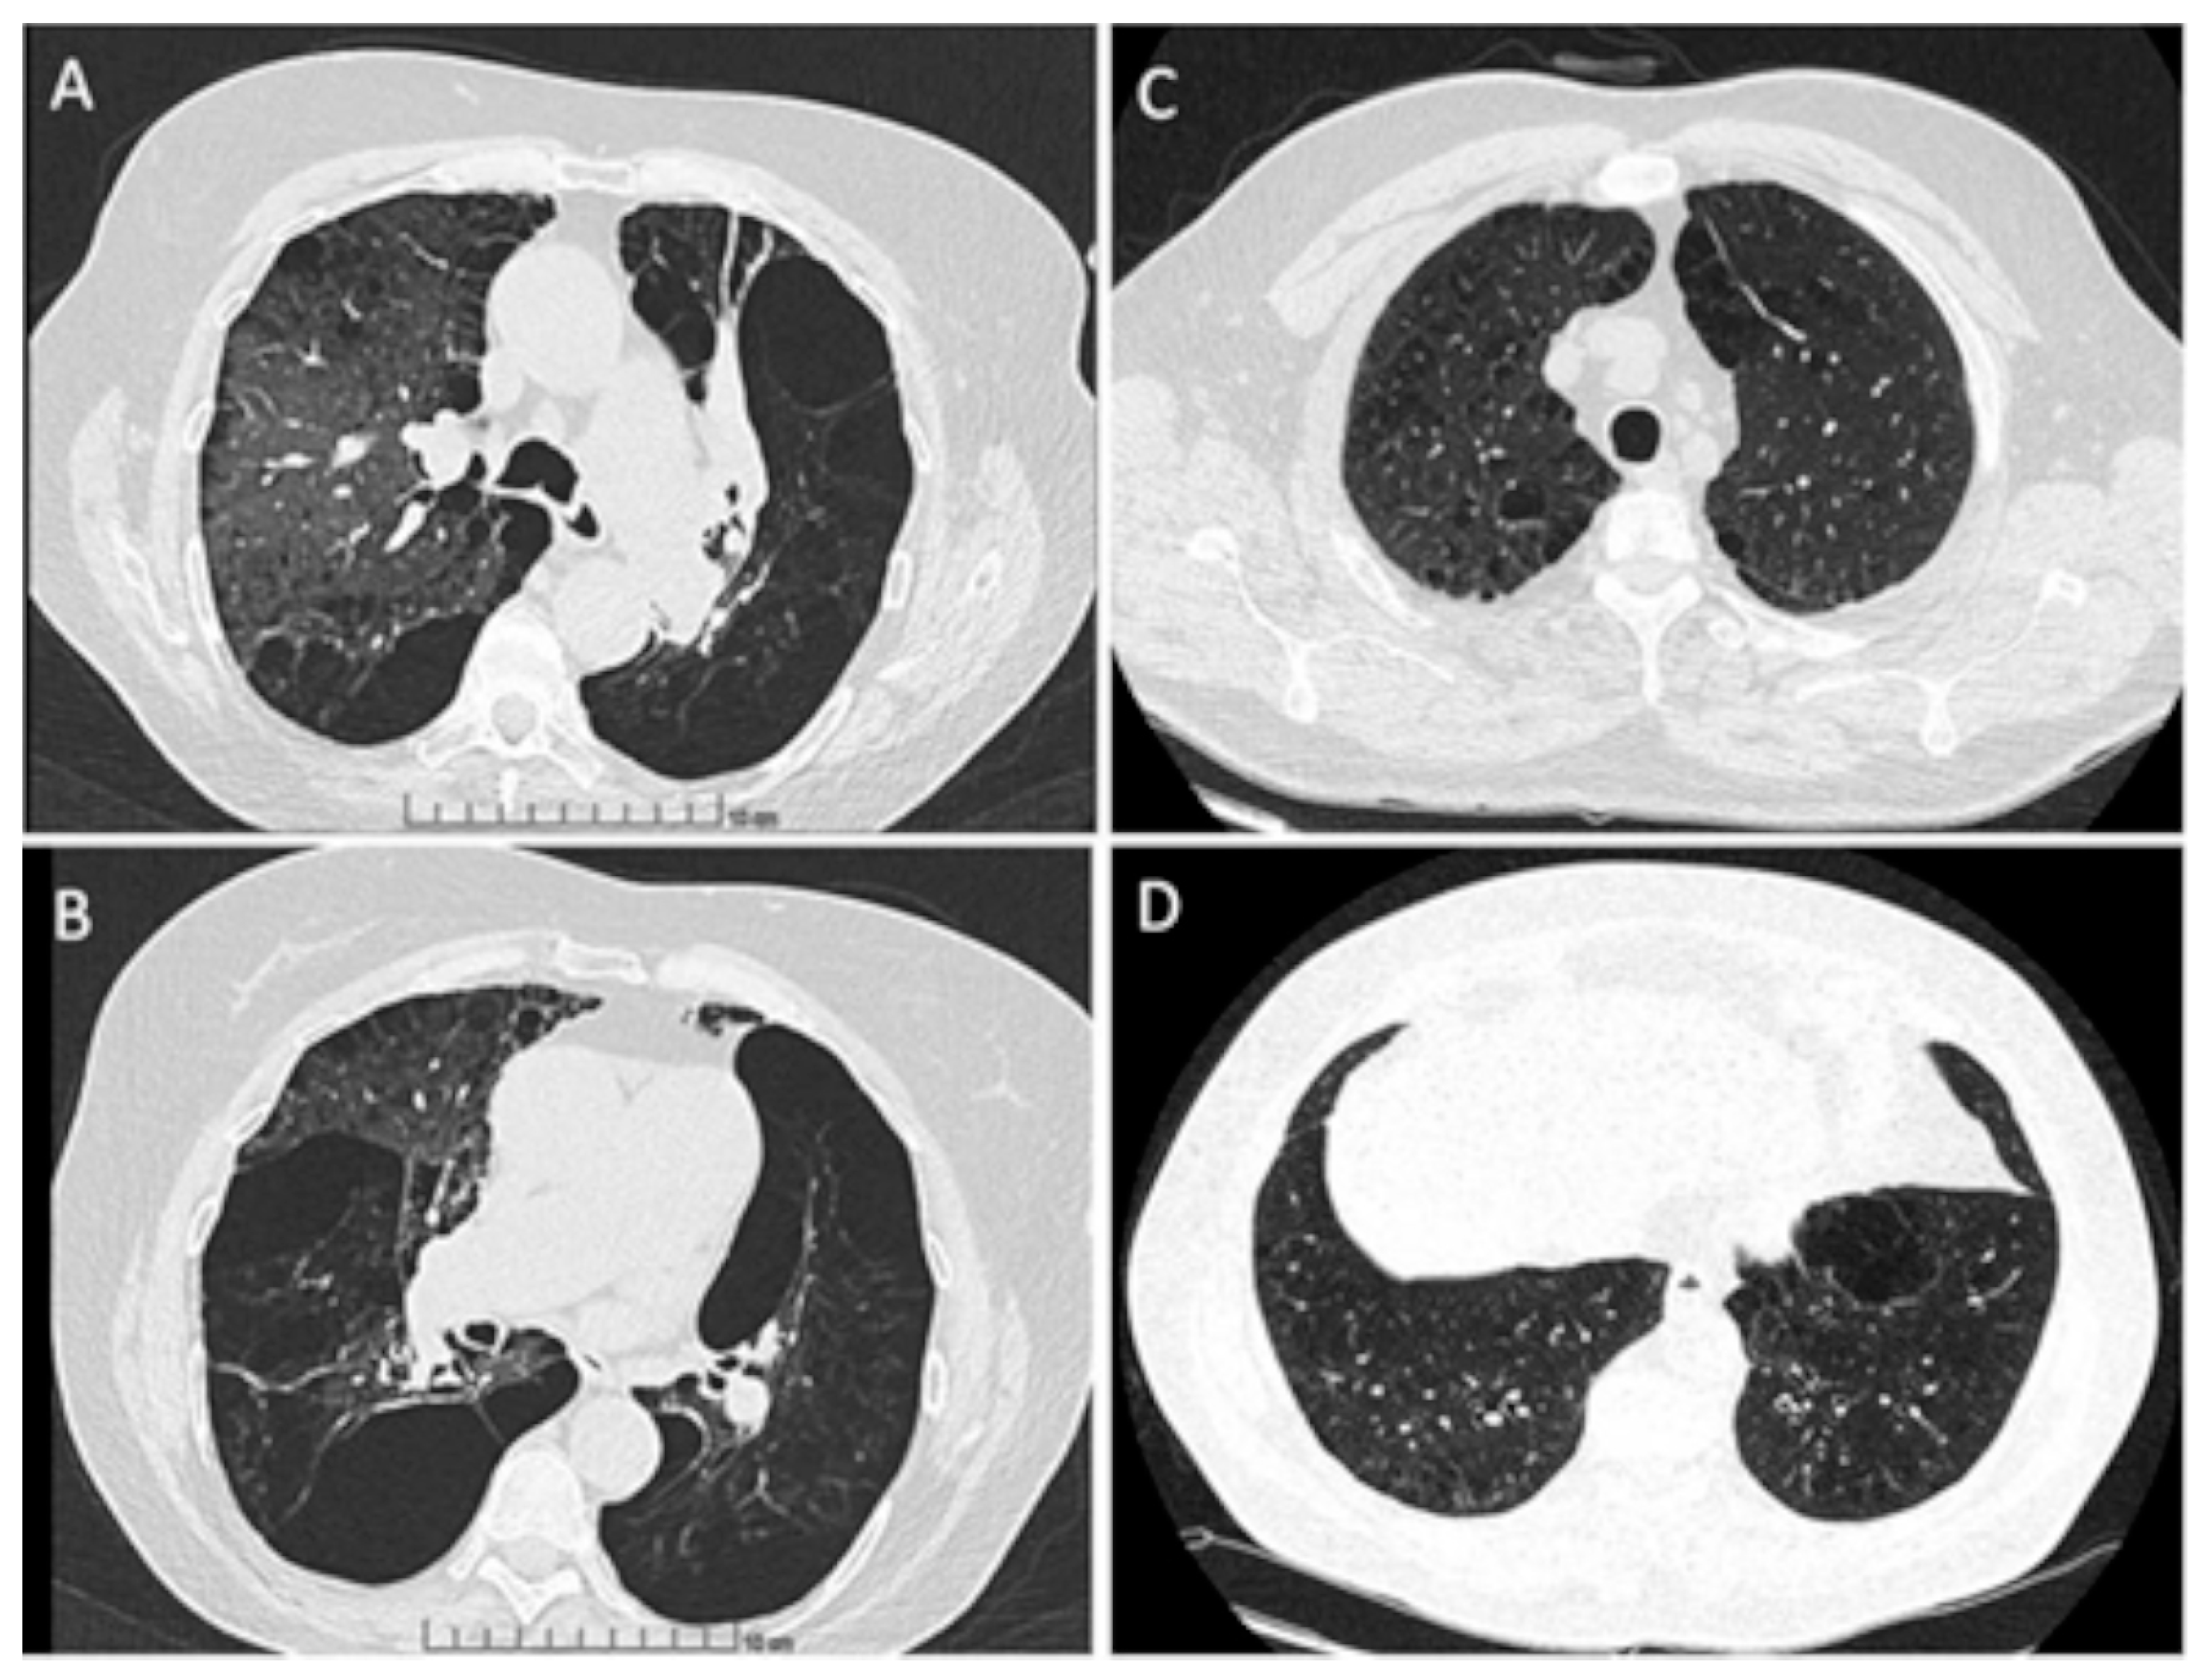

Some examples of HRCT features of PI*M heterozygous patients are shown in Figure 1.

Figure 1. Chest high-resolution CT scan; axial view of upper lobes (A) and lower lobes (B) of lungs of an active smoking patient with M/MProcida genotype; axial view of upper lobes (C) and lower lobes (D) of lungs of a never smoker patient with M/I genotype.